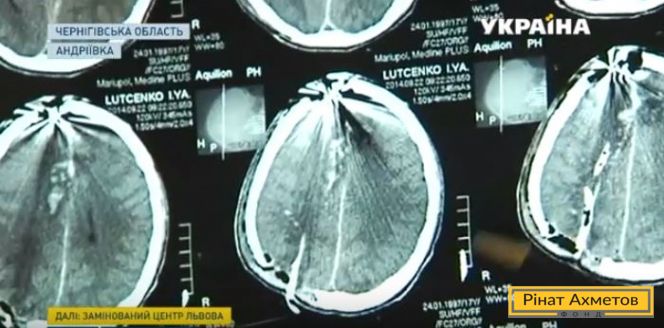

Снайпер прострелил голову студенту из Мариуполя, но он выжил. Врачи называют это чудом. Илью Луценко ранили осенью 2014-му. Парень перенес несколько операций и сейчас проходит реабилитацию. Подробнее в сюжете канала «Украина».